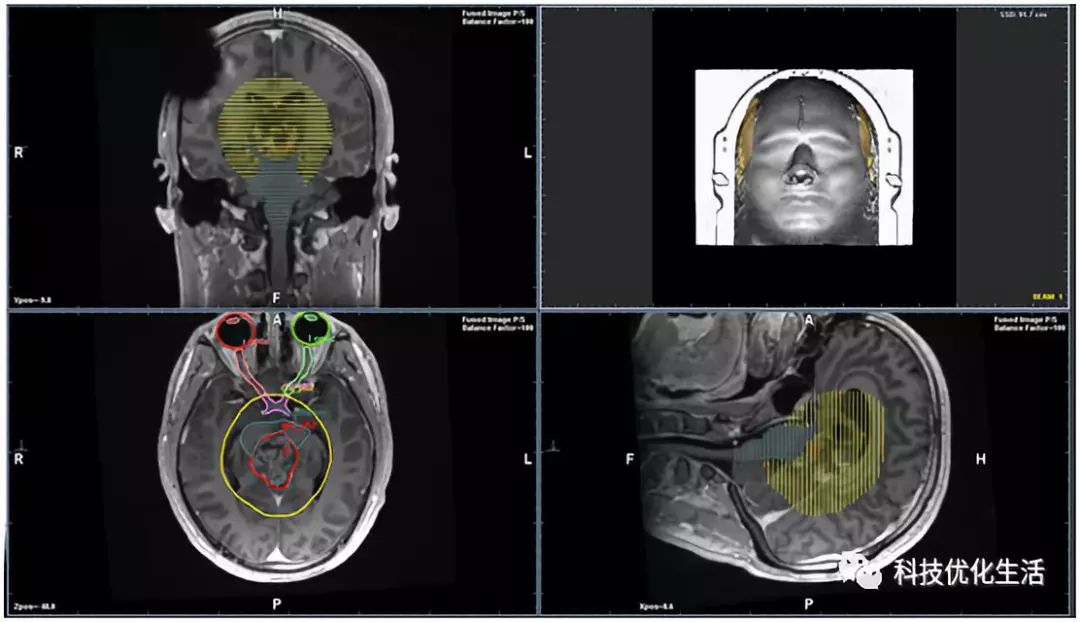

谷歌DeepMind团队在研究如何利用AI更好地将放射疗法应用到癌症治疗中。现在的医生只能通过自身经验以及现有的研究设定该治疗法的辐射量。DeepMind正在跟伦敦大学学院医院合力开发一套能够将这一过程自动化的人工智能系统。未来,新系统能帮助医生缩短切割时间。

来自英国剑桥大学的神经肿瘤学家Raj Jena在过去的六个月中,使用名为InnerEye的AI系统标记前列腺癌患者的扫描结果。扫描完成后,图像被匿名化并加密发送到InnerEye程序,即可描述相关结果情况,并创建3D模型。该软件通过大量的机器学习,目前已经学会了如何标记器官和肿瘤,大大为前列腺癌治疗节省了时间(男人的福音啊)。